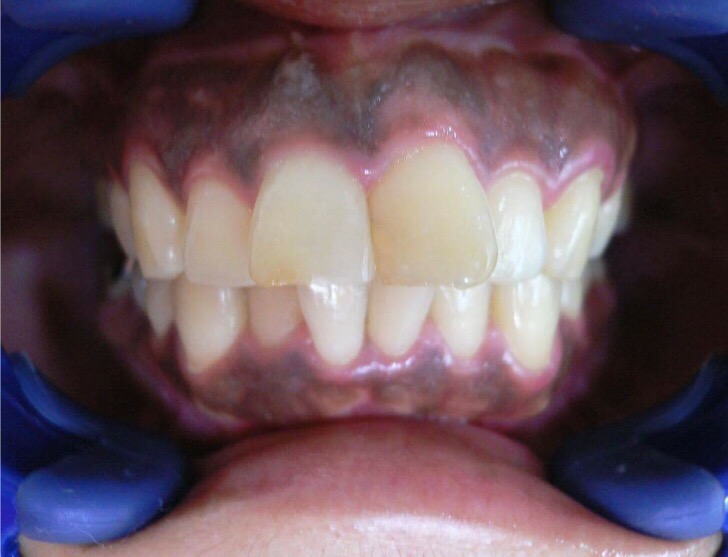

歯ぐきの黒ずみを健康的なピンク色に☆

2016.10.31 コラム 審美歯科に関する記事

みなさま、こんにちは! いつも読んでくださりありがとうございます(*^-^*) 突然ですが・・・ 皆...